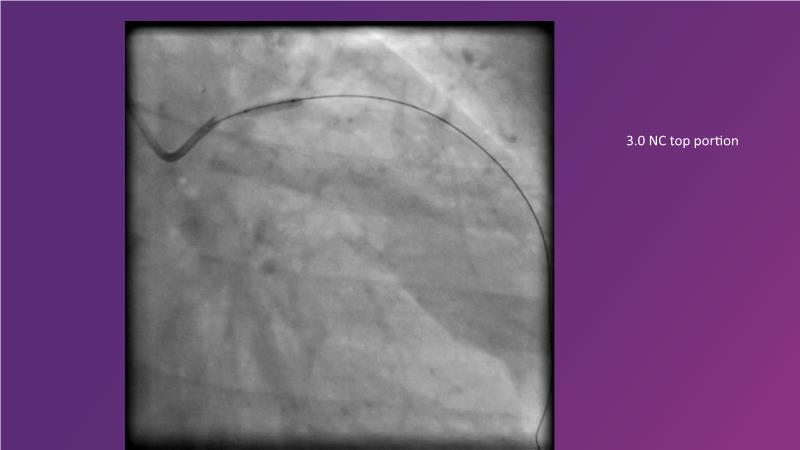

Complex coronary artery disease: can stents and DCB be complementary?

DES and DCB, can these two technologies be complementary for the treatment of the same patient? What are the advantages and how to proceed? You will know everything by watching this presentation based on concrete cases.

- To discuss cases when DCB and DES are complementary